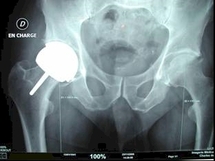

Les prothèses ASR associent un couple métal sur métal, un modèle réputé résistant, mais qui a l'inconvénient de pouvoir libérer des particules de cobalt et chrome. Elles ont montré un taux de reprise (réintervention) plus important que d'autres prothèses.

Les prothèses ASR ont été introduites dans le monde en 2003 et en France en 2004. Près de 93.000 ont été posées, dont 380 en France, selon l'agence des produits de santé (Afssaps). Près de 100.000 prothèses de hanches sont implantées chaque année en France, dont environ 7% de prothèses métal-métal.